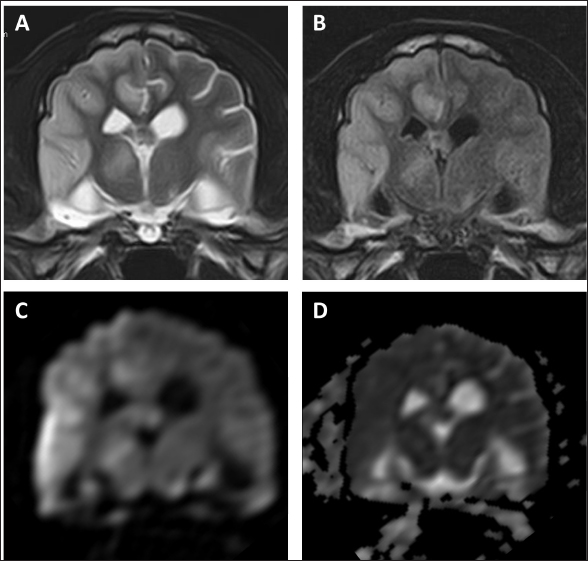

As intracranial disease was suspected in the present case, magnetic resonance imaging (MRI) using a 1.5 Tesla superconducting unit (Vantage Elan, Canon Medical Systems, Otawara, Japan) was performed as further investigation on day 5. MRI revealed a solid mass in the left frontal lobe that the lesion was 32.4 × 29.9 × 27.7 (length × width × height) mm in size showing homogeneous contrast enhancement that shifted the brain midline to the right in contrast enhancement T1-weighted image (T1WI) (Fig. 1A–C). Continuity with the meninges was observed at the tumor margin on contrast-enhanced T1WI. High-signal intensity findings in the brain parenchyma around the tumor indicate edema and/or inflammation on T2-weighted imaging (T2WI) and fluid-attenuated inversion recovery (FLAIR) images. Cerebrospinal fluid was not collected because increased intracranial pressure was suspected based on the MRI findings of transtentorial herniation. MRI findings indicated the possibility of meningioma or HS, and the owner requested surgical volume reduction and medical treatment with anticancer drugs. Radiotherapy was refused because of the cost, and prednisolone (PREDONINE tablets 5 mg; Shionogi & Co, Osaka, Japan) was prescribed at 1 mg/kg once a day until the operation. On day 26, an MRI examination was performed again, revealing that the lesion had grown to 34.7 × 29.9 × 34.9 mm (Fig. 1D–F). The next day, a surgical biopsy due to transfrontal craniotomy was performed to reduce intracranial pressure and confirm the diagnosis. The dog was premedicated with maropitant (1 mg/kg; Cerenia, Zoetis Japan, Tokyo, Japan), fentanyl (3 μg/kg; Fentanyl Injection 0.5 mg, Terumo Corporation, Tokyo, Japan), and lidocaine (2 mg/kg; Lidocaine Intravenous Injection 2%, Terumo corporation), all administered intravenously (IV). General anesthesia was induced with propofol (Propofol Intravenous Injection 1%, Maruishi Pharmaceutical, Osaka, Japan) to facilitate IV until intubation could be performed, following which propofol-based total intravenous anesthesia accompanied by constant rate infusions of fentanyl (10 to 15 μg/kg/hr) and medetomidine (1 to 3 μg/kg/hr; Dorbene, Kyoritsu Seiyaku Corporation, Tokyo, Japan) was administered to maintain anesthesia. Methylprednisolone sodium succinate (10 mg/kg; Solu-Medrol, Pfizer Japan, Tokyo, Japan) and fructose-supplemented glycerol (GLYCEOL for I.V. Infusion, TAIYO Pharma, Tokyo, Japan) were administered IV for 30 minutes to ensure neuroprotection and intracranial pressure reduction, respectively, during the intraoperative period. Although the tumor was visible on craniotomy, it bled easily, and only a small amount of tissue was collected. MRI was performed after surgery, but no significant changes were observed in the size of the tumor (Fig. 2). After the procedures, the patient was allowed to recover from anesthesia and emerged uneventfully 1 hour after extubation. Postoperative management comprising a crystalloid fluid infusion, prednisolone (2 mg/kg once a day), and zonisamide (Epiless tablet, Kyoritsu Seiyaku Corporation, Tokyo, Japan) at 3 mg/kg twice daily was additionally prescribed.

Fig. 1. Postcontrast transverse (A, D, G), dorsal (B, E, H), and sagittal (C, F, I) T1WI of the case. Each image revealed a solid mass in the left frontal lobe.

On day 99, the patient presented with acute onset of somnolence and recumbency. Cerebral infarction was suspected because the entire right cerebral hemisphere and part of the thalamus showed high signal intensity on T2WI and FLAIR images, high signal intensity on diffusion weighted Imaging (DWI) images, and equal signal intensity on the ADC map (Fig. 4). MRI at this time demonstrated that the HS lesion in the left frontal lobe was 28.1 × 24.3 × 22.2 cm in size and had clearly regressed (Fig. 1G–I). The patient was also prescribed rivaroxaban (0.25 mg/kg, twice a day; Xarelto tablets 10 mg; Bayer Yakuhin, Osaka, Japan), and the owners were instructed to perform follow-up at home. The patient's neurological symptoms gradually improved, and a third dose of ACNU was administered at 20 mg/m2 on day 110. However, on day 124, an MRI was performed because a neurological examination revealed a decrease or loss of facial sensation, and trigeminal nerve injury was suspected. Although a contrast agent could not be used because the procedure was performed without anesthesia, clear re-enlargement of the HS lesions was observed (Fig. 5). ACNU was therefore changed to temozolomide (Temozolomide Tablets 20 mg “NK,” Nippon Kayaku, Tokyo, Japan), which was administered at an oral dose of 120-140 mg/m2 once daily for 5 days over a 28-day cycle on day 131, 153, and 173. During this time, there were no major changes in the patient's clinical symptoms, and the patient was able to walk with some unsteadiness. However, the patient died suddenly on day 195. A pathological autopsy was not performed at the owner's request.